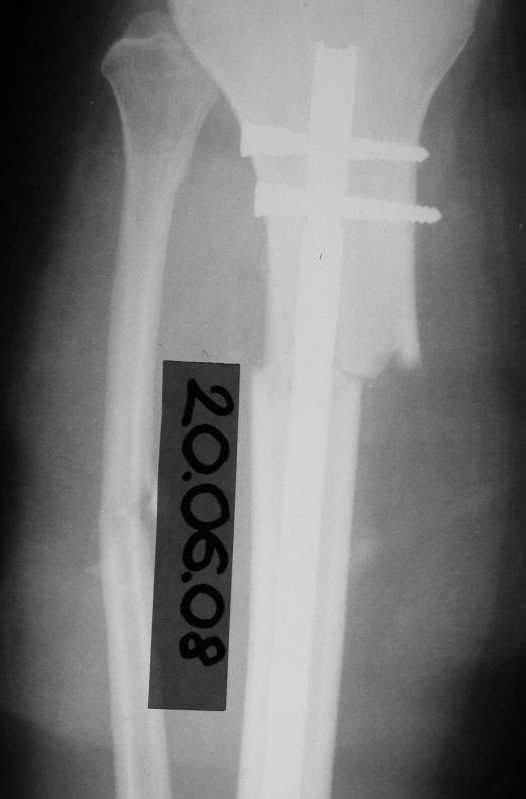

История следующая: женщина (медработник)сбита машиной 7.06.08 - о.перелом обоих костей голени в/3 со смещением. В ПДО ПХО раны,вытяжение за пяточную кость. После заживления раны 20.06.08 выполнен остеосинтез блокирующем стержнем. в течение первого месяца после травмы сохранялась субфебрильная температура на фоне приема антибиотиков. Затем температура стабилизировалась.Б-ая как положено ходила в гипсе на костылях. На контрольных рентгенограммах консолидация не достигалась, иммобилизация продлевалась. Пациентка на себе опробовала все препараты костной регенерации. В марте удален один из фиксирующих винтов. На сегодняшний день идет 11 мес. после травмы. Решается вопрос о инвалидности. Буду благодарен за предложения по дальнейшему ведению больной. Операция?

-зачем так глубоко погружать гвоздь - не боитесь проблем при удалении?

- почему блокирующие винты введены снаружи - рана или другая причина?

- куда, вернее как исчезло смещение на передне-задней проекции?

И наконец, судя по снимкам - гвоздь SIGN, или я ошибаюсь? У нас есть опыт их применения при похожих переломах (8-10 случаев) - все срастались не менее 7-8 месяцев, часто требовали динамизации и пр.